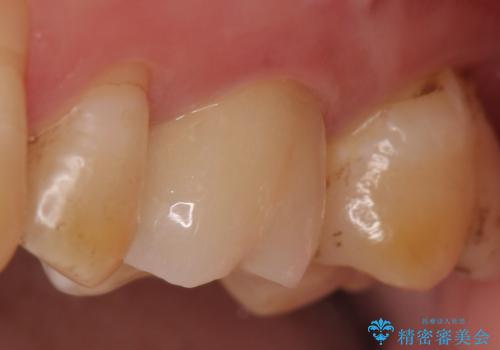

- ものを咬むと左上の奥歯が痛むので診て欲しいといらっしゃった方の症例です。

診査の結果、左上6が失活(歯の神経が死んでいる状態)しており根尖病変を認めたため、根管治療を行いました。

根尖病変の縮小及び症状の消失を確認後、オールセラミッククラウンによる補綴を行いました。